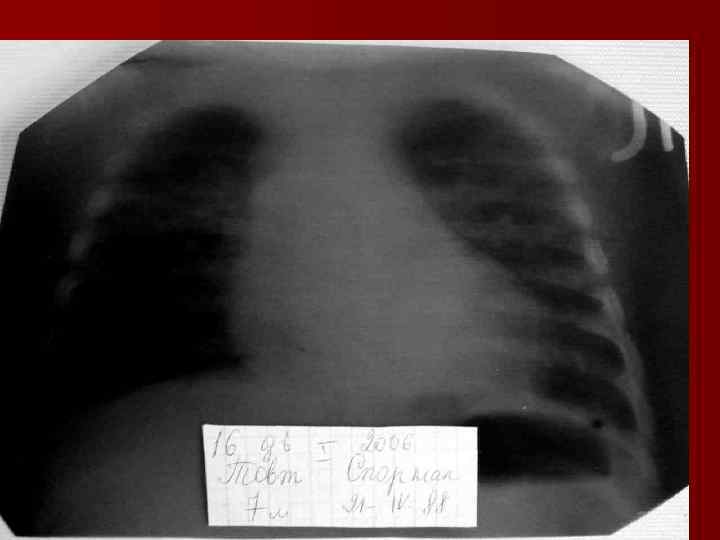

Долевая пневмония характеризуется лобарным пневмоническим инфильтратом. Крупозная ( пневмококковая) пневмония диагностируется прежде всего по клиническим данным. Крупозная пневмония сохраняет свою типичную картину пневмококковой пневмонии: острое начало с характерными клиническими данными, циклическое течение, несклонность к деструкции, гомогенной и лобарной инфильтративной тенью при рентгенологическом исследовании. Вместе с тем, широкое использование антибиотиков способствовало значительному снижению числа крупозных пневмоний у детей. Интерстициальная – редкая форма пневмоний, при которой оказывается поражен прежде всего интерстиций. Как правило, интерстициальная пневмония обусловлена вирусами, пневмоцистами, внутриклеточными микроорганизмами и грибами.

Морфологическую форму пневмонии определяют по клинико – рентгенологическим данным: выделяют очаговую, очагово – сливную, долевую ( крупозную), сегментарную и интерстициальную пневмонии. Очаговая – наиболее распространенная форма. Пневмонические очаги чаще бывают размером 1 см и более. Очагово – сливная – инфильтративные изменения в нескольких сегментах или во всей доле легкого, на фоне которых могут быть видны более плотные участки инфильтрации и/или полости деструкции. Сегментарная – в процесс вовлекается весь сегмент, который, как правило, находится в состоянии гиповентиляции, ателектаза. Морфологическая картина воспаления при очаговых и сегментарных пневмониях связана с первичным инфекционным воспалением в бронхах, что дает основание отнести эти варианты поражения легочной ткани к бронхопневмониям, нередко сопровождающихся бронхообструктивным или бронхообтурационным синдромами. В настоящее время данный тип пневмоний у детей встречается наиболее часто.

Т. о. пневмония, как инфекционно – воспалительное заболевание паренхимы легких характеризуется: * общей реакцией организма на инфекцию ( признаки интоксикации – ухудшение общего состояния, аппетита; лихорадка и др. ) локальными изменениями в легких при физикальном обследовании ( очаговым укорочением перкуторного тона, ослаблением дыхания, локальными хрипами и др. ); * инфильтративными затемнениями на рентгенограммах, которые ранее отсутствовали ( при этом нет других известных причин возникновения затемнения при рентгенологическом исследовании легких) обусловленными заполнением альвеол экссудатом, содержащим преимущественно полинуклеарные нейтрофилы; *кашлем; * дыхательной недостаточностью – ДН ( одышка, участие вспомогательной мускулатуры в акте дыхания и др. ) * развитием внелегочных осложнений ( поражение сердечно – сосудистой системы, ЦНС, почек и т. д. ).